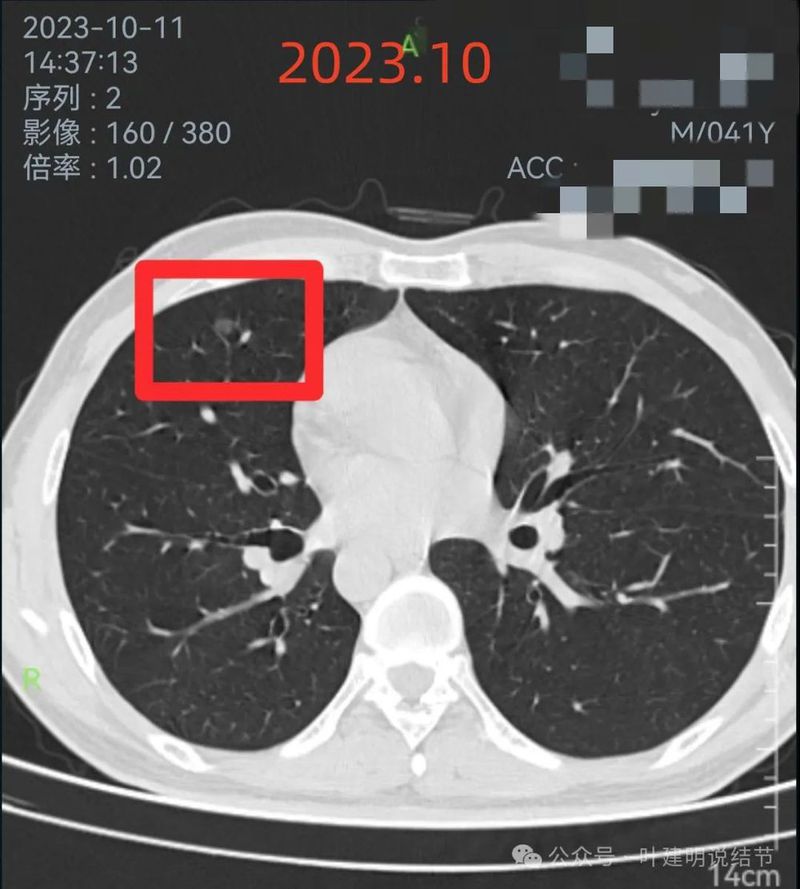

2023年10月时右侧病灶没有明显进展。

2023年10月时左侧病灶较前略明显,便仍觉得密度从高到低有移行,由于整体轮廓较前明显,恶性的可能性增加了。

红色的就是报告上所主要的病灶,右肺中叶的,这个病灶是磨玻璃结节,整体轮廓清楚,瘤肺边界也清,是要考虑是肿瘤范畴的。但是它密度低,没有实性成分,目前风险还不大,还没有到一定要干预的程度,或许在观察三年5年8年也不见得一定会进展。我的想法是再观察一下,半年到一年之间复查都可以。蓝色的界限欠清,实性部分密度过高,像炎性点。意见供参考!